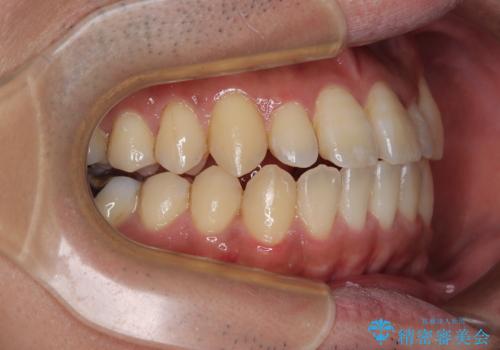

内側に引っ込んだ歯を治したい インビザラインの矯正治療

- 前歯のデコボコとクロスバイトを治したいとのことで来院された患者様です。

上下顎ともに歯列全体の側方拡大とIPR(歯と歯の間を削る)によってデコボコとクロスバイトが解消するように設計し、インビザラインにより治療を行うこととしました。

反対咬合特有の治療途中の前歯の干渉が長く続き、治療中に食事をとりにくく、ご迷惑をおかけしました。

前歯の咬み合わせの調整などを行い、安定した咬み合わせに仕上げることができました。